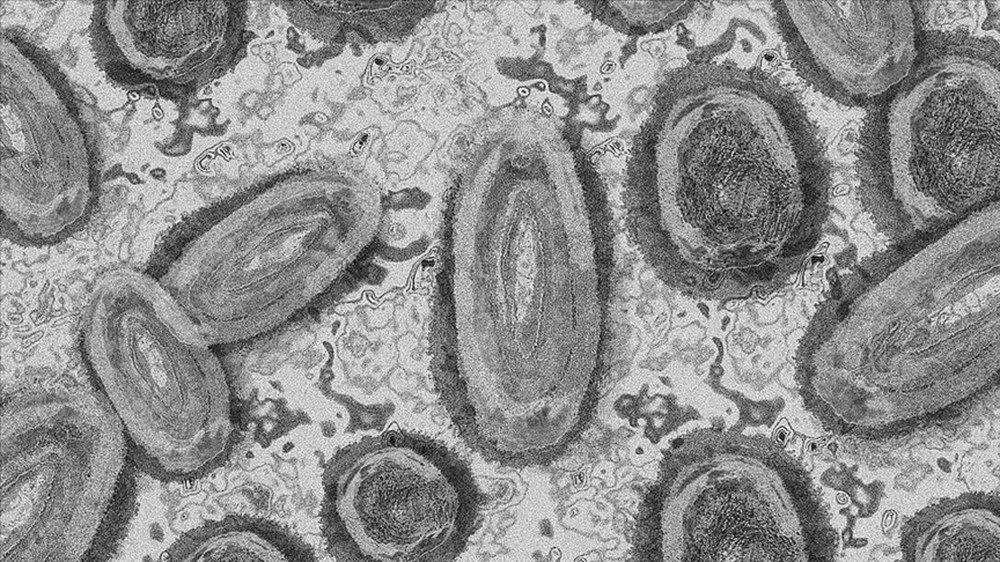

M ÇİÇEĞİ NEDİR?.

M çiçeği, klinik olarak daha hafif olmasına rağmen, semptomları geçmişte çiçek hastalarında görülenlere benzeyen, nadiren ölümcül olabilen, hayvandan insana bulaşan viral bir hastalıktır. İnsandan insana da bulaşabilmektedir.